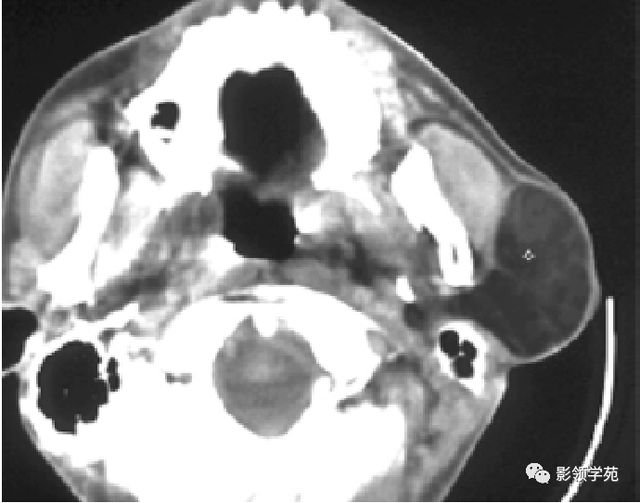

图6 a 、b 、c 囊腺癌 左侧腮腺弥漫性增大,密度增高,边缘无法确定,同侧颈部可见淋投合肿大坏死,胸锁乳突肌受侵占